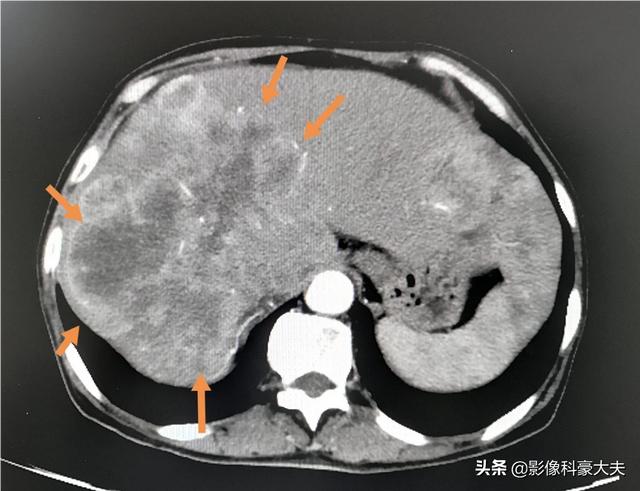

Les métastases hépatiques géantes multiples comme celles-ci peuvent progresser en peu de temps si elles ne sont pas contrôlées ou si elles sont insensibles au traitement.